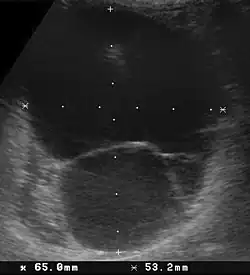

Aufgrund der Besonderheit des Kalziumstoffwechsels neigen Meerschweinchen zur Bildung von Harnsteinen (Urolithiasis). Bei Meerschweinchen bestehen etwa 85 % der Steine ganz oder überwiegend aus Calciumcarbonat, meist in Form von Calcit, seltener auch Vaterit. Diese Calciumcarbonatsteine haben häufig einen Calciumphosphatanteil, es handelt sich also um Mischsteine. Bei Blaseninfekten können aufgrund von Ureasebildnern auch Struvitbeimengungen auftreten, bei oxalsäurereicher Fütterung auch Calciumoxalatsteine.[3] Sie führen zu Reizung der Schleimhaut der Harnwege und eventuell auch zu bakterieller Sekundärinfektion durch aufsteigende Keime, wobei insbesondere eine Harnblasenentzündung (Zystitis) entstehen kann. Eine Zystitis kommt vor allem bei über 2 Jahre alten Weibchen vor. Die Folge sind Schmerzen beim Wasserlassen (Strangurie) und häufiger Harnabsatz (Pollakisurie), eventuell mit Blutbeimengungen. Die Analregion ist dann häufig nass und es besteht die Gefahr eines Fliegenmadenbefalls (Myiasis). Die Steine können aber auch zur Verlegung der Harnwege führen, worauf die Harnbildung (bei Nierenbecken- und Harnleitersteinen) sowie der Harnabsatz (bei Blasen- und Harnröhrensteinen) nicht mehr möglich ist (Anurie). Sind der Harnblasenausgang oder die Harnröhre verlegt, füllt sich die Harnblase bis zum Bersten (Notfall).